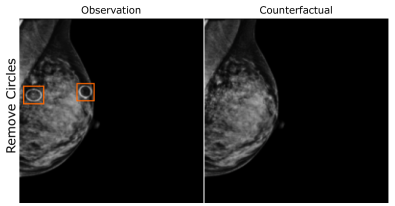

EMBED

Using prior insights, we apply our mechanisms to a real-world artefact removal task on the EMory BrEast imaging Dataset (EMBED) (Jeong et al., 2022). Schueppert et al. (2024) observe that triangular and circular skin markers are spuriously associated with breast cancer in classifiers due to shortcut learning (Geirhos et al., 2020), and manually labelled 22,012 affected mammograms. Using this dataset, we train a significantly scaled-up, amortised, anti-causally guided semantic mechanism () to remove skin markers. We model triangular markers (), circular markers (), breast density (), and cancer () as independent parents of the mammogram , and remove artefacts by intervening on and while holding and fixed. Figure 6 shows that our mechanisms effectively remove artefacts and can disentangle representations for triangles and circles. We successfully remove of triangles and of circles in our test set - a noteworthy result given the dataset’s small size and the scarcity of labelled skin markers (Appendix I).